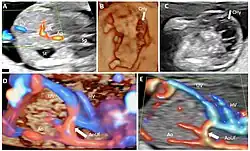

Doppler ultrasonography is medical ultrasonography that employs the Doppler effect to perform imaging of the movement of tissues and body fluids (usually blood),[1][2] and their relative velocity to the probe. By calculating the frequency shift of a particular sample volume, for example, flow in an artery or a jet of blood flow over a heart valve, its speed and direction can be determined and visualized.

Duplex ultrasonography sometimes refers to Doppler ultrasonography or spectral Doppler ultrasonography.[3] Doppler ultrasonography consists of two components: brightness mode (B-mode) showing anatomy of the organs, and Doppler mode (showing blood flow) superimposed on the B-mode. Meanwhile, spectral Doppler ultrasonography consists of three components: B-mode, Doppler mode, and spectral waveform displayed at the lower half of the image. Therefore, "duplex ultrasonography" is a misnomer for spectral Doppler ultrasonography, and more exact name should be "triplex ultrasonography".[3]

Colour Doppler shows the direction of the blood flow in red or blue (either towards or away from the transducer). Meanwhile, spectral Doppler not only shows the direction of blood flow, it also shows the phases (pulsatility) and acceleration of the blood flow. Any sudden changes in direction of blood flow produces audible sounds on the ultrasound machine.[3]

In spectral Doppler, the y-axis shows the direction and velocity of the flow. Meanwhile, the x-axis (as known as "baseline") shows the flow over time. The gradient at any point on the waveform would therefore shows the acceleration of the flow. In "antegrade" flow, the blood flows according to the normal flow within the circulatory system (e.g. veins flow towards the heart while arteries flows away from the heart). In "retrograde" flow, the flow would reverse (e.g. veins flow away from heart or arteries flow towards the heart). However, "retrograde" flow can be both abnormal or normal. For example, in portal hypertension, there is an abnormal portal venous flow where it flows away from the liver (hepatofugal flow) instead of the normal flow towards liver (hepatopetal flow). In jugular venous pressure waveform of the internal jugular vein, the retrograde "a" waveform is a normal flow due to right atrium contraction. Both antegrade or retrograde flow can be either towards or away from the probe transducer, depending on the position of the probe relative to the blood flow. Blood flow toward the transducer would appear above the baseline while blood flows away from the transducer will appear below the baseline. Waveform of the flow can be classified as: pulsatile (as in arteries), phasic (as in veins), non-phasic (as in diseased veins), and aphasic (no flow). Spectral broadening (thickness of the waveform) increases from large vessels (plug flow) to medium vessels (laminar flow) to small/stenotic/diseased vessels (turbulent flow) due to a larger variety of blood with different ranges of velocities in those with turbulent flow.[3]